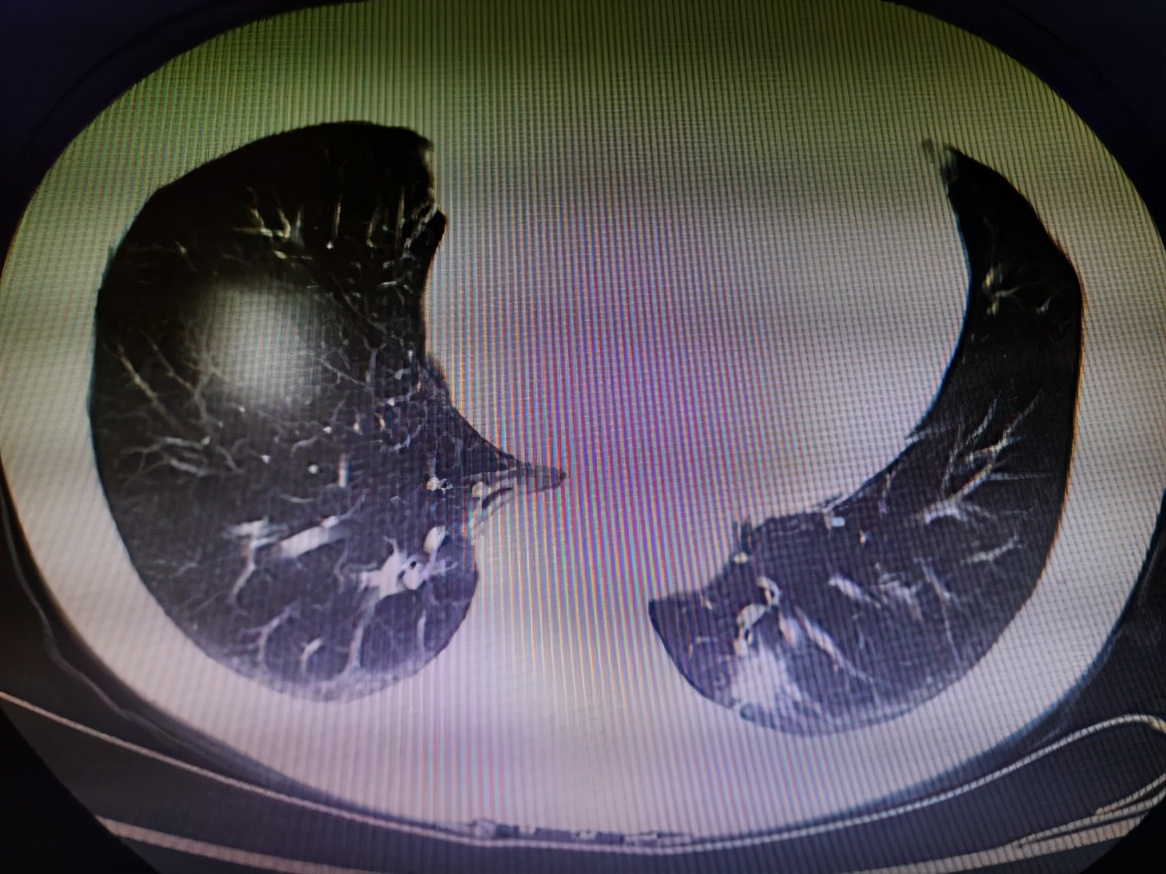

该患者在体检时发现左下肺部位有一个 2 公分左右的肺结节,在医生的建议下前往重庆市璧山区人民医院胸心外科就诊。完善检查后,评估为肺恶性肿瘤的可能性极大,必须及时切除。

对于绝大部分肺恶性肿瘤及部分肺良性疾病患者来说,最常见的治疗方式是开展肺叶切除手术。近年来,胸腔镜肺叶切除术迅速发展,逐渐取代了传统的「开胸切肺」,然而当前国内开展该技术仍以三孔或者四孔法为主。

「实际上,该手术可以只通过一个单孔完成全部操作,即术中胸腔镜和操作器械均从一个孔进出,完成肺叶切除全部流程。」胸心外科艾成博士介绍,单孔胸腔镜下肺叶切除手术对患者的损伤更小,切口也更加美观。

「通过在手术中进行快速冰冻活检,20 分钟即可判断患者是否为恶性肿瘤,然后利用仅 3 到 4 厘米的单孔胸腔镜,切除肿瘤的同时,对周围脂肪组织进行彻底清扫。」艾成说,该技术不仅可以减少患者的检查程序,还能最大限度减轻手术产生的不良反应,术后创伤更小、疼痛更轻、恢复更快。

在艾成博士的主刀下,科室团队成功为该患者开展单孔胸腔镜下肺叶切除手术+系统淋巴结清扫术。手术仅耗时两小时,术中出血不到 50 ml,手术切口仅 3 cm,患者恢复良好,很快就能出院,很好地体现了「快速康复」理念。